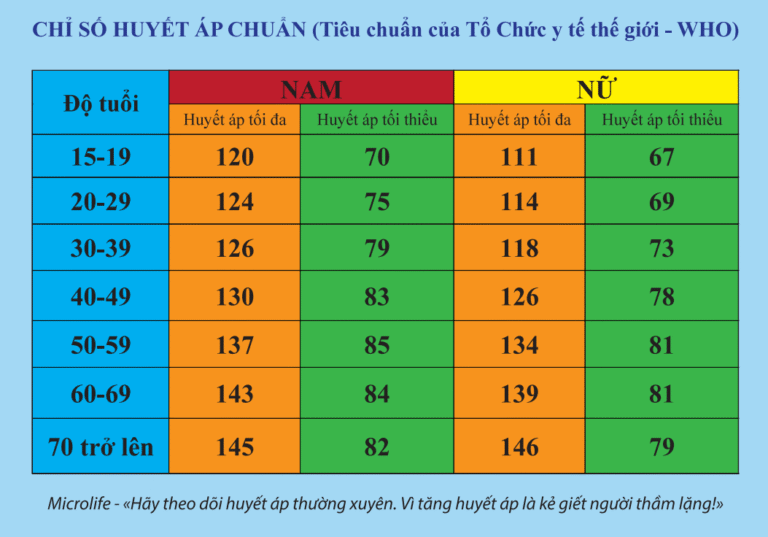

Huyết áp là một chỉ số quan trọng phản ánh sức khỏe…